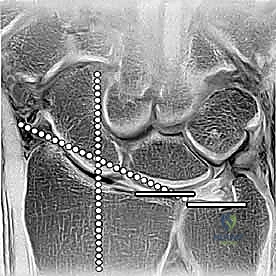

تعد الكعبرة البعيدة بمثابة الدعامة الأساسية الحاملة للوزن في الرسغ، حيث تنقل ما يقدر بنحو 75% إلى 80% من الحمل المحوري من اليد إلى الساعد. أما نسبة الـ 20% إلى 25% المتبقية، فتحملها الزند البعيد والمثلث الغضروفي الليفي (TFCC).

لذلك، فإن أي تغيير، ولو كان طفيفًا، في تشريح الكعبرة البعيدة يؤثر بشكل عميق على ميكانيكا الرسغ، مما قد يؤدي على المدى الطويل إلى تآكل الغضاريف، الألم المزمن، وتطور الفصال العظمي (الخشونة المبكرة). يتكون السطح المفصلي للكعبرة من انحناءات دقيقة تتناسب مع عظام الرسغ (العظم القاربي والهلالي)، ويجب استعادة هذا السطح بدقة متناهية لتجنب المضاعفات المستقبلية.

يعتمد الدكتور محمد هطيف على أحدث التقنيات التشخيصية، حيث يبدأ بـ الأشعة السينية (X-rays) في وضعيات متعددة. وفي حالات الكسور المعقدة التي تمتد إلى داخل المفصل، يتم إجراء تصوير مقطعي محوسب (CT Scan) لبناء صورة ثلاثية الأبعاد للكسر، مما يساعد في التخطيط الجراحي الدقيق.

3. إرجاع الكسر (Fracture Reduction)

تُعد هذه الخطوة الأهم. باستخدام أدوات دقيقة وجهاز الأشعة السينية المباشر في غرفة العمليات (C-arm fluoroscopy)، يقوم الدكتور هطيف بإعادة ترتيب شظايا العظام إلى مكانها التشريحي الأصلي، مع التركيز الشديد على استواء السطح المفصلي.